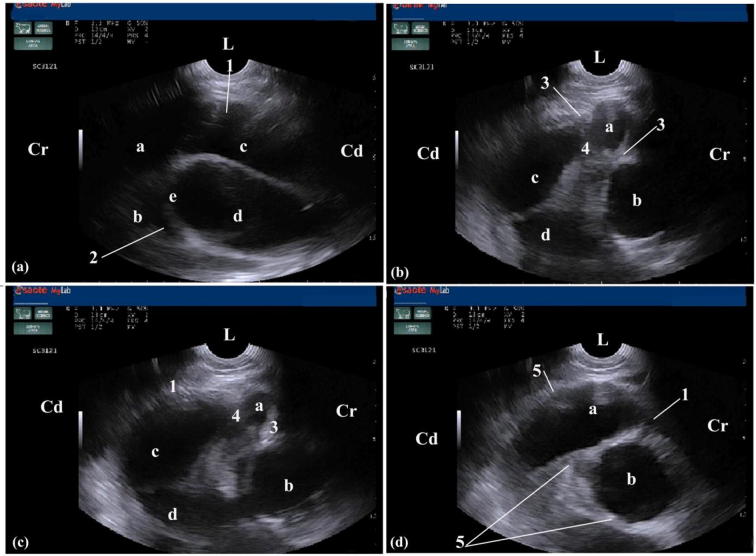

Fig. 6.

Ultrasonograms in a 3-year-old female buffalo with traumatic pericarditis. Imaging was performed from the left 4th. intercostal space (ICS) at the midway point between the elbow and shoulder points and showing hypoechoic exudates in the pericardium, accumulation of echogenic fibrinous deposits within the myocardium and around the atrioventricular valves and thickening in the wall of atria. ICS: Intercostal space; L: left; Cr: Cranial; Cd: Caudal; A: Right atrium; B: Left atrium; C: Right ventricle; D: Left ventricle; E: Atrioventricular valve [AV valve]; 1: hypoechoic exudates; 2: thickening of AV valve; 3, 4: echogenic fibrinous deposits; 5: thickening of atria walls with echogenic fibrinous deposits.

Thoracic ultrasonographic findings included cardiomegaly, thickened cardiac wall with deformity in the characteristic recognisable cardiac shape. Accumulation of hypoechoic fluids (usually pus) was interspersed with echogenic deposits of fibrin within the pericardium. Thickening in the myocardium and deposition of echogenic fibrinous aggregations with hypoechoic fluids on the ventricles, atria and valves were also detected. Echogenic bands were imaged within the heart with severe reduction in its contractility (Figs. 8a, b). The characteristic ultrasonographic findings of TP in buffaloes were summarized in Table3.

Fig. 8.

Ultrasonograms in a 5-year-old female buffalo with traumatic reticuloperitonitis and pericarditis. Images were taken from the left 4th ICS at the midway point between the elbow and shoulder points showing cardiomegaly, deformity of its characteristic recognisable shape and thickened cardiac wall. ICS: Intercostal space; L: left; D: dorsal; Vt: Ventral; Cr: Cranial; Cd: Caudal; 1: thoracic wall; 2: Heart; 3: Echogenic bands; 4: Hypoechoic exudates within the pericardium and fibrinous echoic deposits within atria and ventricles; 5: Thickening in cardiac wall; 6: Atria; 7: Ventricles.